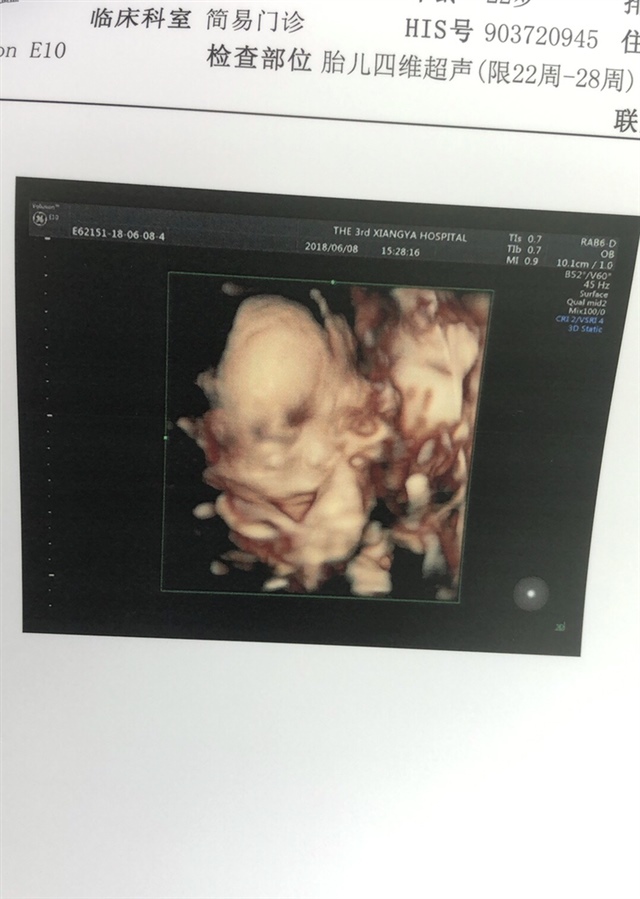

孕24周+2天

男